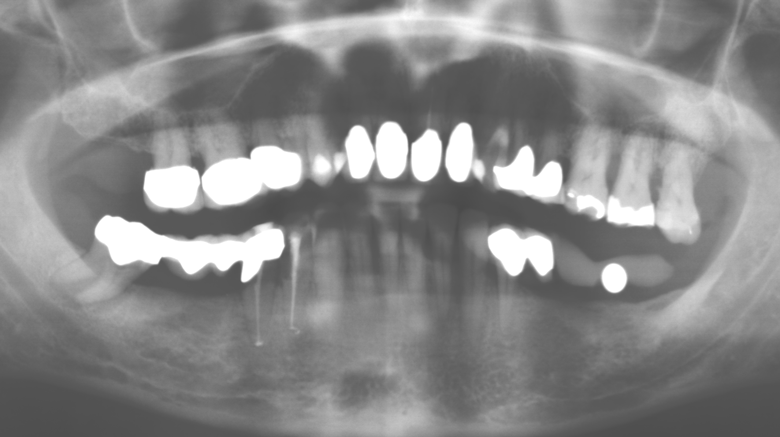

Fig. 1: Panoramic radiograph of initial situation in 2004.

Description of patient case

A 52-year-old patient presented in our clinic for the first time in 2004 following tooth loss in the third quadrant, expressing a desire for a new prosthetic restoration. Periodontal and radiological diagnostics revealed the need for extensive periodontological treatment. In addition, teeth 48, 28 and 27 were attributed a very poor prognosis and were subsequently extracted (Fig. 1). Following the successfully completed, systematic periodontological treatment, a fixed dental implant was inserted with the introduction of five implants in tooth regions 35, 36, 37, 46 and 47. Prosthetic treatment of the natural teeth was effected with veneered zirconium dioxide ceramic crowns; the implants were composed of two-piece, individual zirconium dioxide abutments and similarly veneered crowns made of a zirconium dioxide ceramic (Cercon base colored, Dentsply Sirona Lab). Definitive insertion of the prosthetic restoration occurred in 2005.